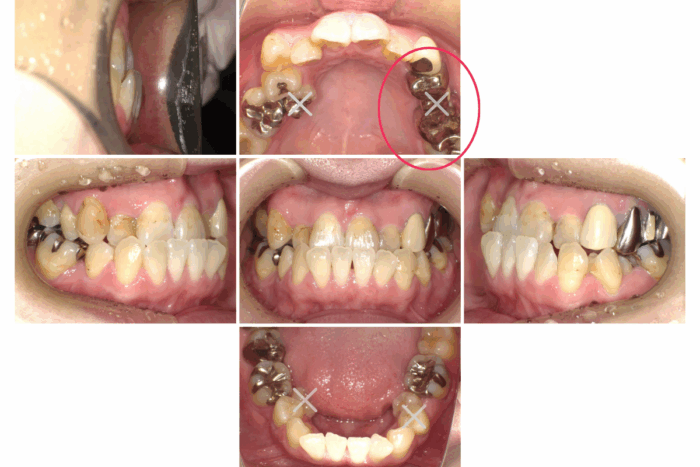

患者さま:30代女性/左上4・5・6番にメタルブリッジ

主訴:歯のガタつき・かみ合わせが反対

矯正治療のために上下左右4本抜歯する必要がありました。そのため、抜歯する歯のうち1本は、ブリッジを分割しポンティック部分(ブリッジの真ん中の人工歯のこと)を除去して代用しました。ワイヤー矯正で歯並びとかみ合わせを改善しました。

- 【症例詳細】

- 主訴:ガタガタと受け口が気になる

- 診断名:叢生・反対咬合

- 初診時年齢:32歳

- 使用装置:ホワイトワイヤー矯正

- 抜歯部位:上顎右側第二小臼歯、下顎右側第二小臼歯、下顎左側第一小臼歯

- 治療期間:2年7ヶ月

- 費用:¥750,000(税込¥825,000)

- リスク・副作用:痛み、歯根吸収、歯肉退縮、むし歯、後戻り